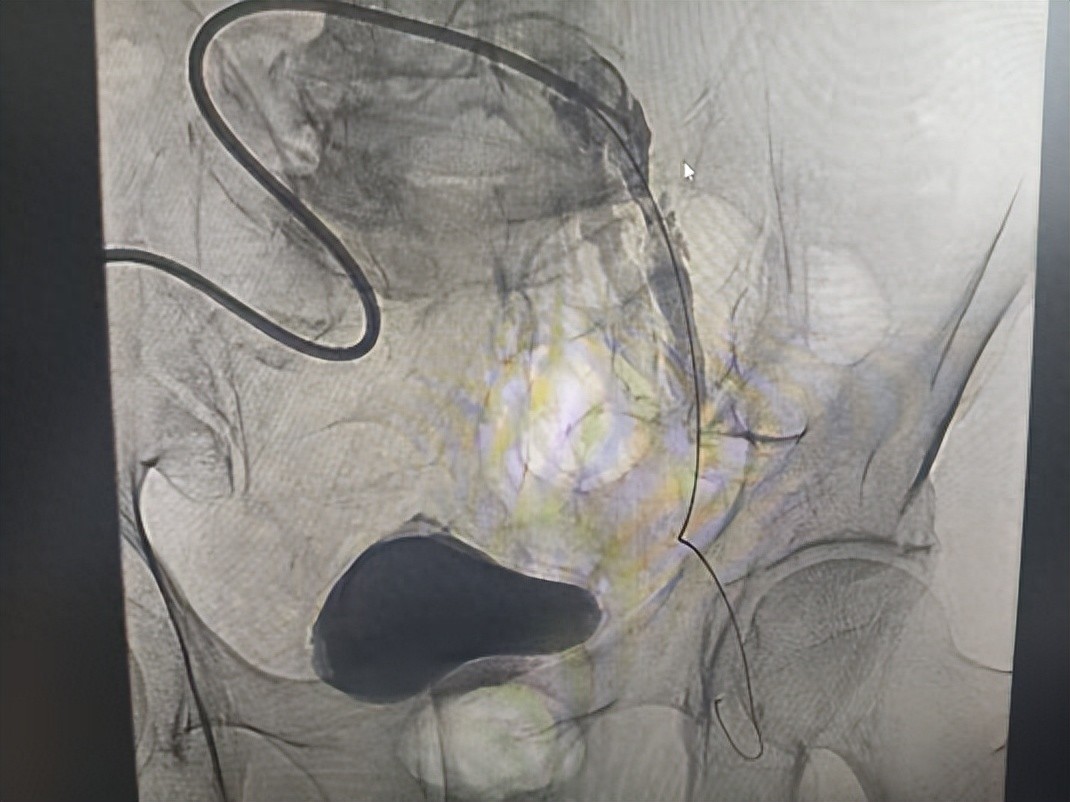

手术当天,在麻醉科等相关科室的全力配合下,专家团队凭借精湛的医术和默契的协作,有条不紊地开展手术,先后完成血管造影、机械取栓、球囊扩张等多项高难度操作。经过5个小时的全力奋战,手术圆满成功,全程没有出现任何并发症!

术后,王先生的左下肢疼痛缓解,皮肤温度明显回升,血管搏动也恢复了正常,肢体供血得到了有效改善,困扰他多日的病痛彻底解除。